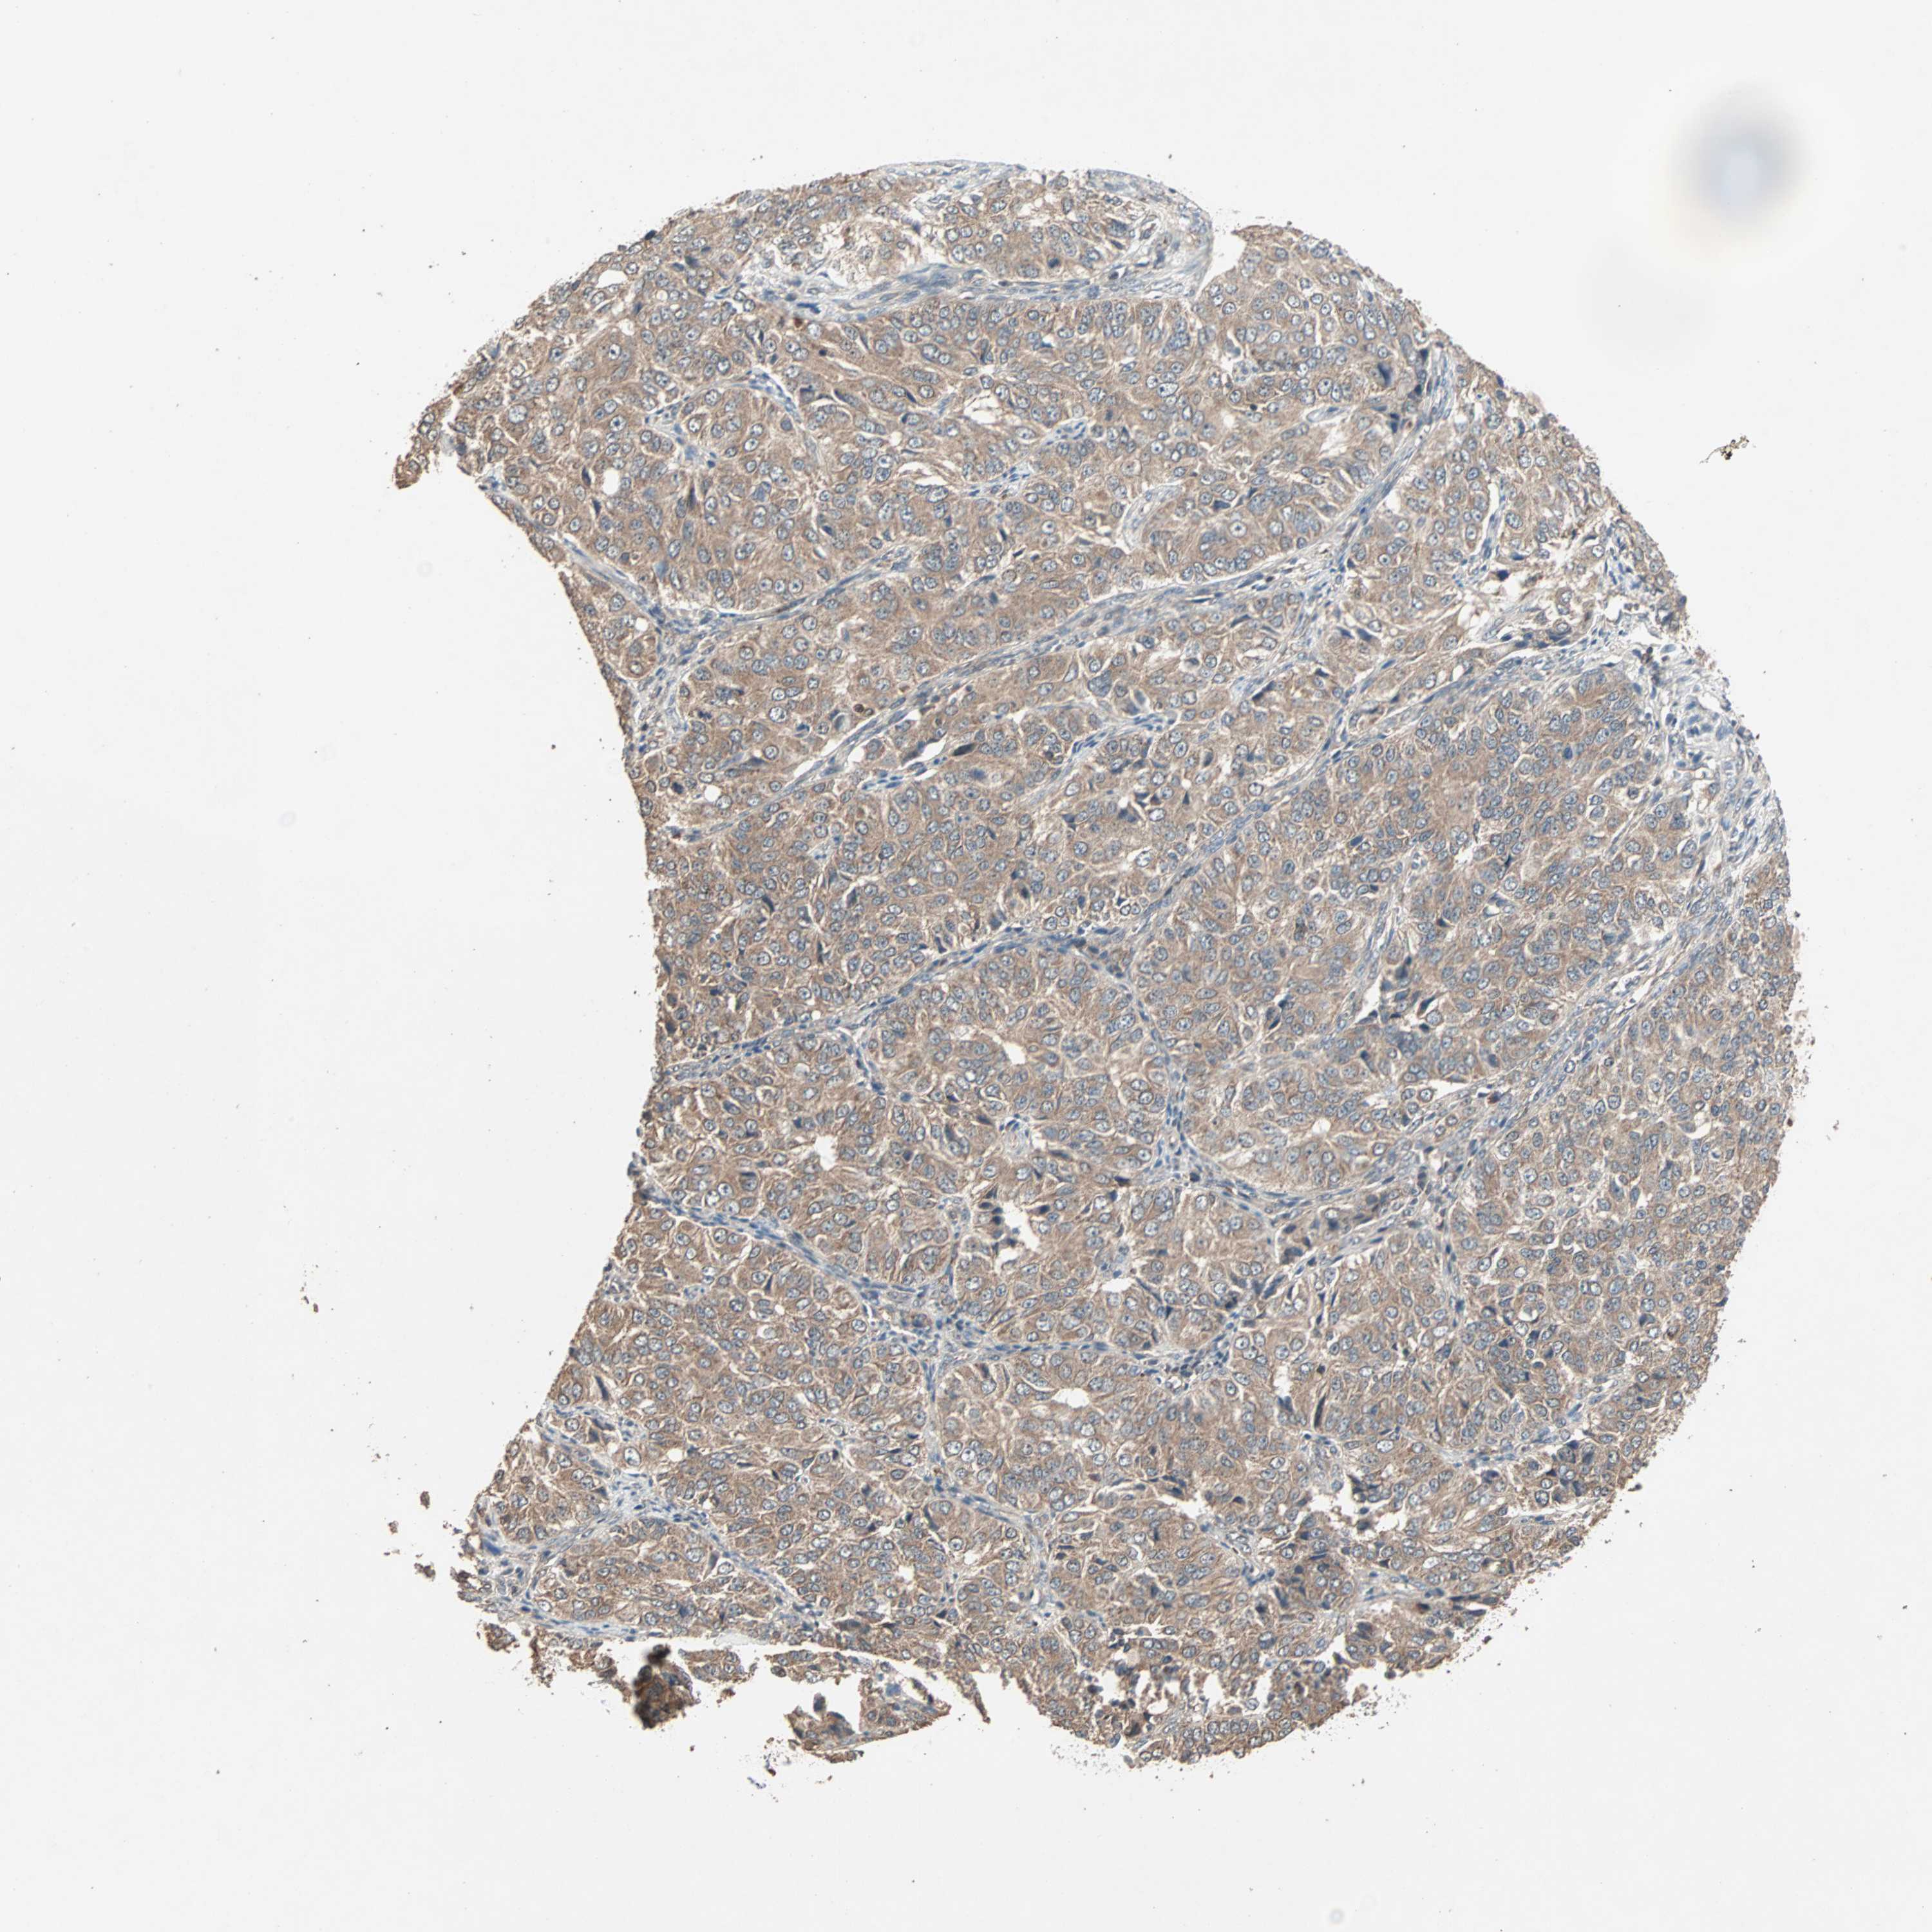

OVARIAN CANCER - Protein expressioni

A mouse-over function shows sample information and annotation data. Click on an image to view it in a full screen mode. Samples can be filtered based on level of antibody staining by selecting one or several of the following categories: high, medium, low and not detected. The assay and annotation is described here.

Note that samples used for immunohistochemistry by the Human Protein Atlas do not correspond to samples in the TCGA dataset.

Antibody stainingi

Antibody staining in the annotated cell types in the current human tissue is reported as not detected, low, medium, or high, based on conventional immunohistochemistry profiling in selected tissues. This score is based on the combination of the staining intensity and fraction of stained cells.

Each image is clickable and will lead to virtual microscopy that enables deeper exploration of all samples and also displays staining intensity scores, fraction scores and subcellular localization as well as patient and tissue information for each sample.

Antibody HPA005651

Staining

High

Medium

Low

Not detected

Intensity

Strong

Moderate

Weak

Negative

Quantity

>75%

75%-25%

<25%

None

Location

Nuclear

Cytoplasmic/membranous

Cytoplasmic/membranous,nuclear

Cystadenocarcinoma, serous, NOS

Carcinoma, endometroid

Cystadenocarcinoma, mucinous, NOS

Carcinoma, NOS